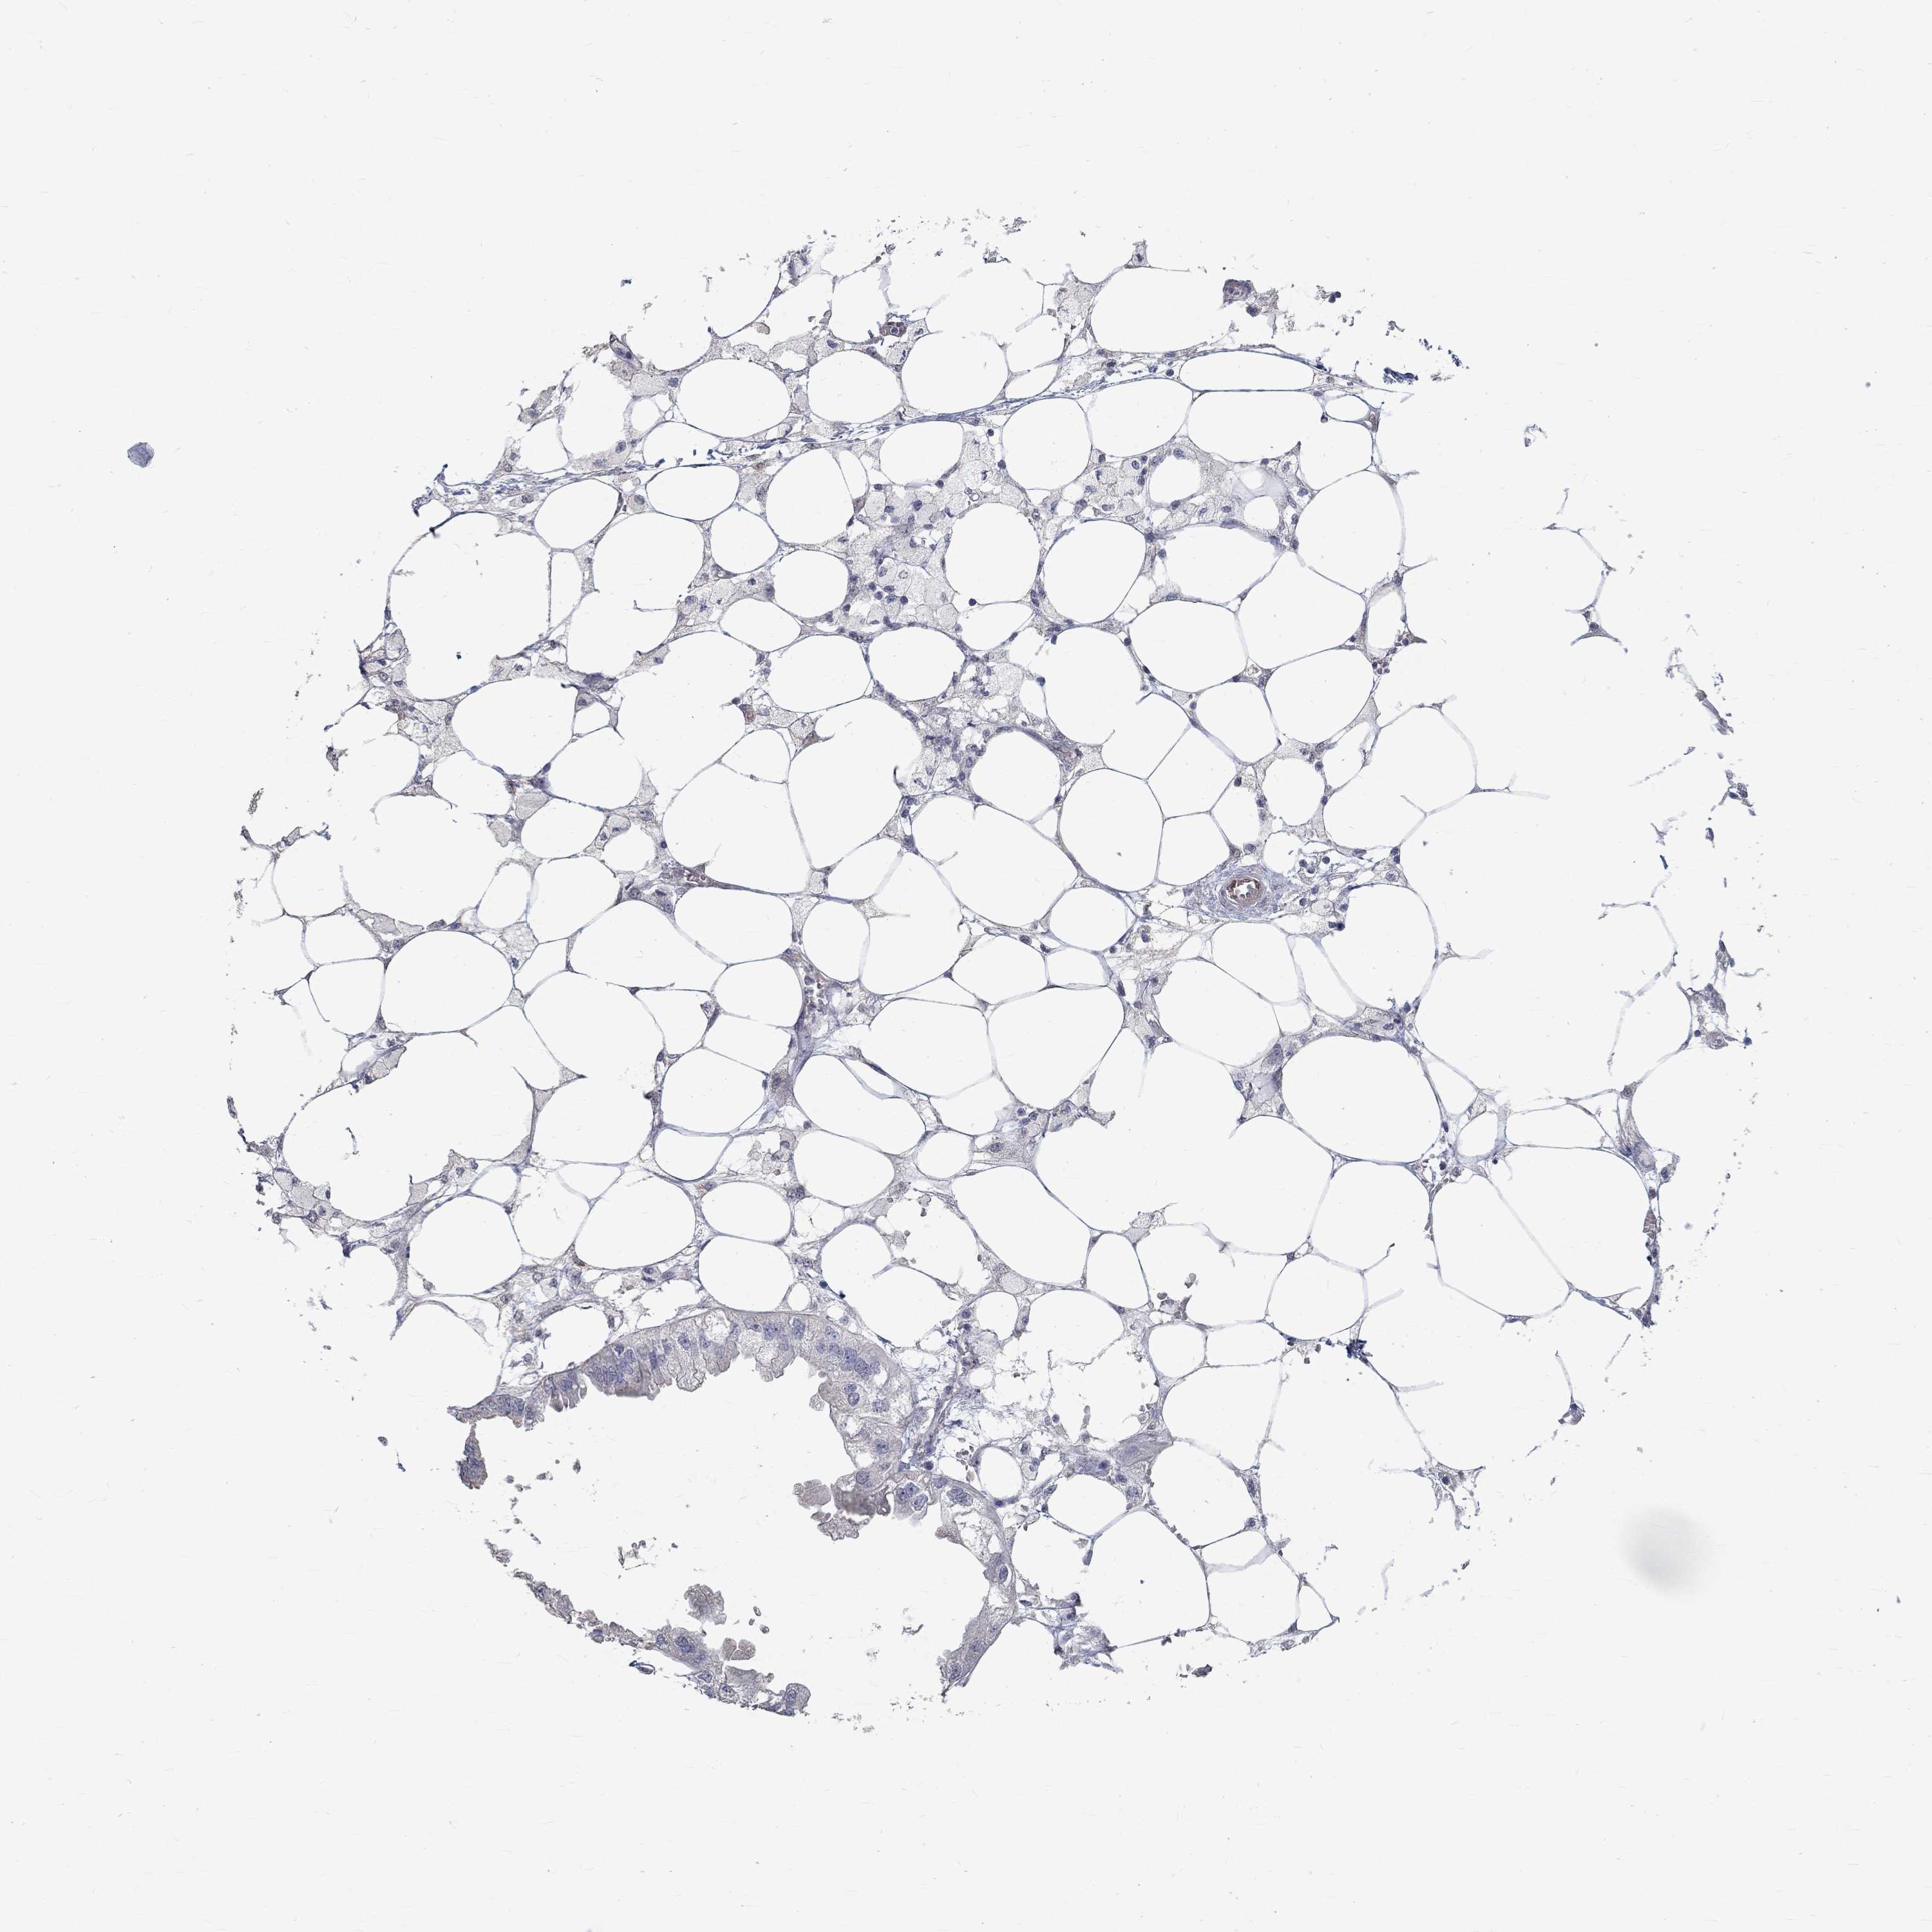

ENDOMETRIAL CANCER - Protein expressioni

A mouse-over function shows sample information and annotation data. Click on an image to view it in a full screen mode. Samples can be filtered based on level of antibody staining by selecting one or several of the following categories: high, medium, low and not detected. The assay and annotation is described here.

Note that samples used for immunohistochemistry by the Human Protein Atlas do not correspond to samples in the TCGA dataset.

Antibody stainingi

Antibody staining in the annotated cell types in the current human tissue is reported as not detected, low, medium, or high, based on conventional immunohistochemistry profiling in selected tissues. This score is based on the combination of the staining intensity and fraction of stained cells.

Each image is clickable and will lead to virtual microscopy that enables deeper exploration of all samples and also displays staining intensity scores, fraction scores and subcellular localization as well as patient and tissue information for each sample.

Antibody HPA065502

Antibody CAB000125

Staining

High

Medium

Low

Not detected

Intensity

Strong

Moderate

Weak

Negative

Quantity

>75%

75%-25%

<25%

None

Location

Nuclear

Cytoplasmic/membranous

Cytoplasmic/membranous,nuclear